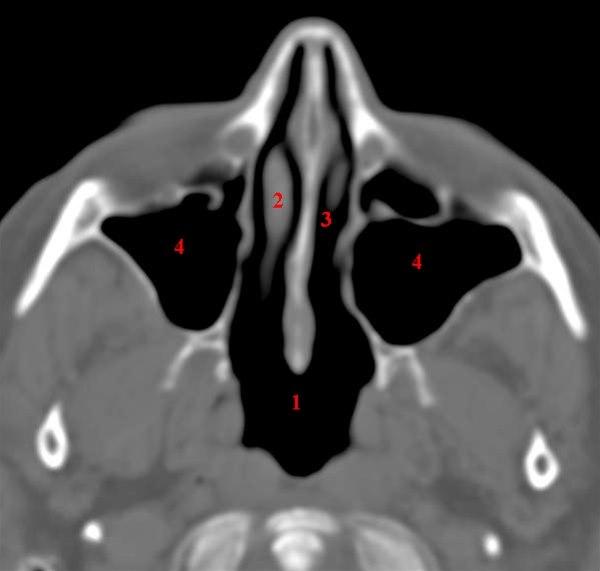

CT-snitt i axialplan gjennom normalt luftførende maxillarsinus (kjevebihuler)

- Nasopharynx

- Nasal conchae

- Nesecavitet

- Sinus maxillaris